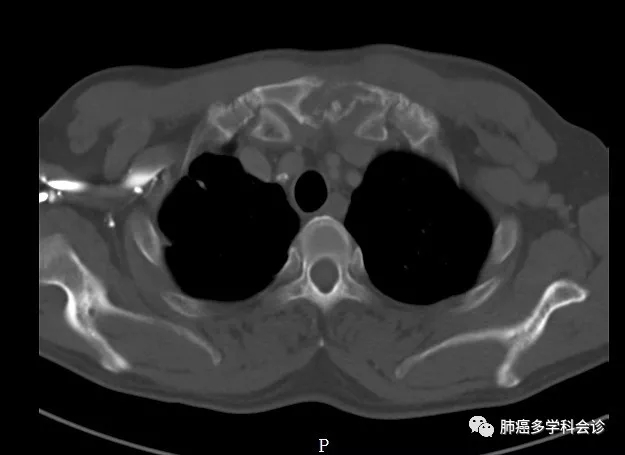

患者张TSH,男,55岁。2018年8月因右胸隐痛、轻咳并体重下降就医,在当地医院做CT发现右上肺占位、纵膈淋巴结肿大,胸骨小转移灶。到我院行CT引导下肺穿诊断为肺腺癌。脑MRI 未发现转移。

基因检测:Kras基因G12A突变